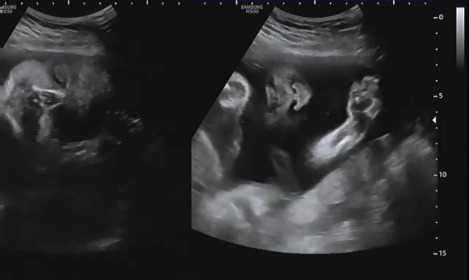

언제나처럼 진료시간에 맞춰 복부초음파로 태아의 상태를 확인했다. 시간이 지나감에 따라 내 품 안에 있던 아기는 초음파상으로 얼굴로 가득 차 보일만큼 성장하였다. 아이의 입이 꼬물거리며 움직이는 모습을 보며 설레는 마음으로 그동안 큰 이상은 없었는지 확인했다. 어느 때와 다름없이 햇님이는 자신이 건강하다는 것을 확인시켜주듯 양팔을 열심히 흔들며 엄마를 안정시켜줬다.

햇님이의 상태를 확인하고 아이의 자세 및 위치를 알려줬다. 다행히 머리가 아래로 향하게 있어 이대로 막달까지만 잘 있어준다면 자연분만이 가능할 것 같다고 이야기했다. 앞으로 짧다면 짧지만 길다면 긴 약 10주간의 시간이 남았는데 그동안 아기가 건강하게 세상으로 나와 만날 준비를 해 주길 희망했다.